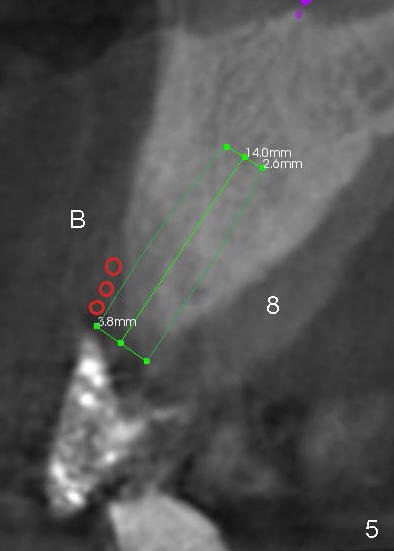

Buccal atrophy at the site of #8 dictates a smaller implant than that of #9 (Fig.4-7).